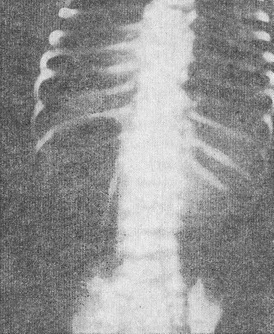

![]() 10. Рентгенограма новонародженого з препилорической атрезією (пояснення в тексті) |

Для уточнення діагнозу проводять рентгенографію черевної порожнини в вертикальному положенні дитини в двох проекціях (прямій та бічній). На рентгенограмах (рис. 10) визначають розширення шлунка з рівнем рідини і повна відсутність газу в петлях тонкої і товстої кишок. Іноді діагноз уточнюють за допомогою контрастної речовини (5-б мл йодолипола), уведеного в шлунок. Відсутність евакуації контрастної речовини зі шлунка є відмінною рисою цієї патології.